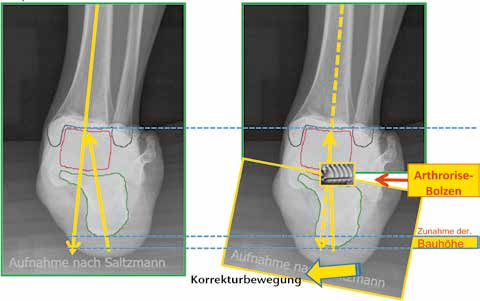

Zuletzt soll noch auf ein Korrekturphänomen hingewiesen werden, welches das postoperative Vorgehen beeinflusst: Durch die Neupositionierung des Calcaneus aus der Valgusfehlstellung in die orthograde Einstellung kommt es zu einer Zunahme der Bauhöhe zwischen dem oberen Sprunggelenk und der plantaren Calcaneusfläche (Abb. 2a u. b). Klinisch relevant wird der sich einstellende Spitzfuß; eine zusätzliche operative Intervention wurde bisher nicht notwendig – allerdings ist dies im Rahmen der Nachbehandlung zu berücksichtigen.

Die Mobilisierung der Patienten ist bereits ab dem 1. postoperativen Tag unter schmerzorientierter Vollbelastung möglich. Dem Vorliegen einer postoperativen Spitzfußeinstellung muss durch eine temporäre Absatzerhöhung begegnet werden (Abb. 3). Dies führte neben einer rascheren Mobilisierbarkeit auch zu einer Reduktion der notwendigen analgetischen Therapie.